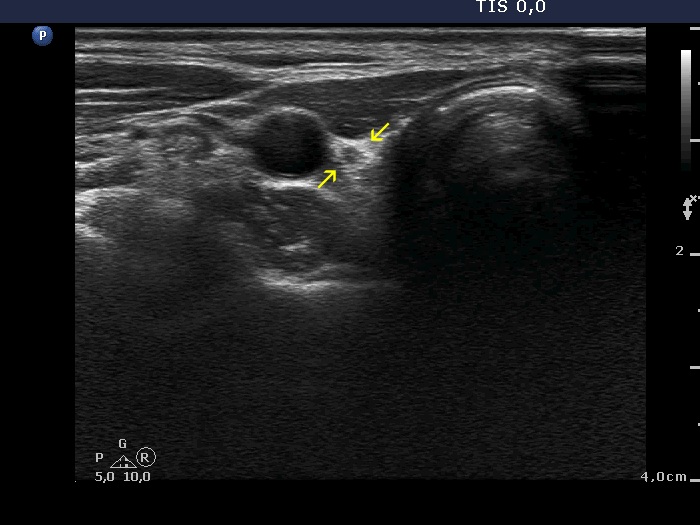

Right lobe, longitudinal scan

Right lobe, transverse view. The tiny hypoechoic area is signed with yellow arrows.